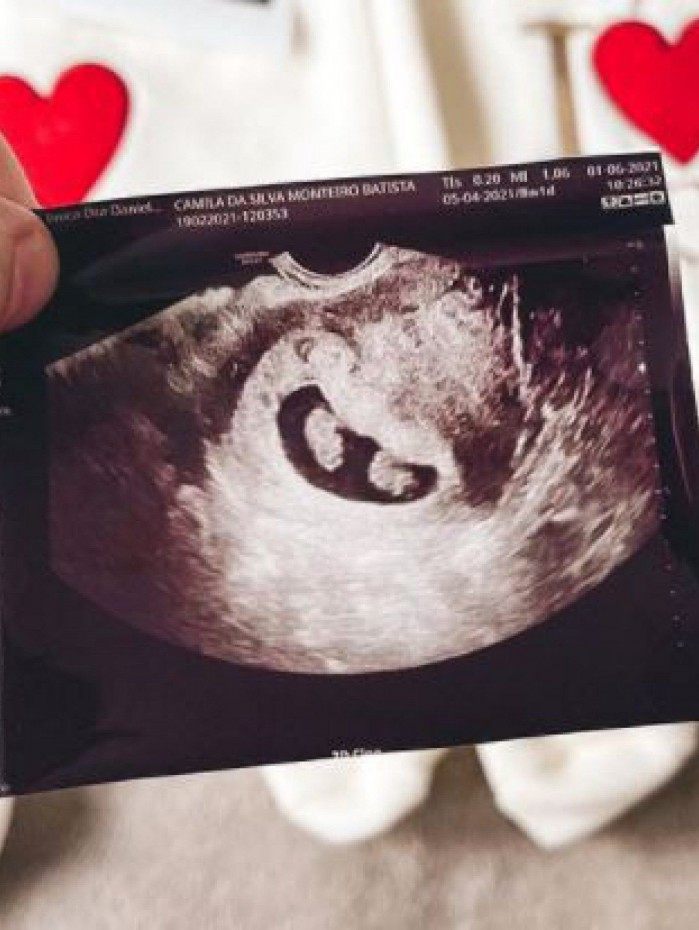

"E as surpresas não acabaram. VAMOS TER GÊMEOS IDÊNTICOS! O Senhor fez o milagre! Pra vocês terem noção, nós colocamos dois embriões no dia da transferência, mas APENAS UM desenvolveu. E esse mesmo embrião SE DIVIDIU NATURALMENTE! Imagina o nosso choque?! Quando é da vontade do Senhor, Ele faz!

Queríamos muito gêmeos e o Senhor nos atendeu de uma forma poderosa e inimaginável! Pra vocês terem noção, a chance disso acontecer é de apenas 3%, independente se for através de FIV ou não! E essa divisão aconteceu de forma espontânea, na FIV não é possível escolher isso. Agora vamos ter duas meninas ou dois meninos! Igualzinhos!", contou a influenciadora que passou por processos de fertilização in vitro.